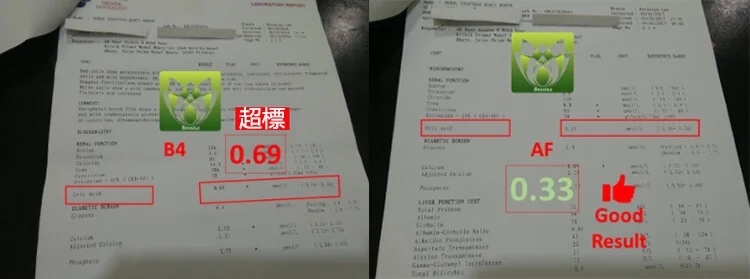

看看這個報告有很大的改善:

B4 AF 标准指数

Urea 19 8.8 ( 2.5 – 6.4 )

Creatinine 186 93 ( 53 – 88 )

CKD-EPI 32 74 ( >90 )

Urid Asid 0.69 0.33 ( 0.16 – 0.36 )

【 醫生嚴重警告他腎臟指數不樂觀 】- 服用後有很大的改善!他說非常有效!

這位是SetapakKL。美國雲杉腎寶片就是他的好朋友推薦他服用的,情況是這樣的:他長期尿酸,痛風,尿液渾濁,尿泡,糖尿病打胰島素,血壓偏高,就在近期體檢報告醫生嚴重警告他腎臟指數不樂觀,飲食一定要注意,阿民就問到有方法解決嗎,他不想要洗腎,醫生跟他說這樣子是可能可以拉長腎臟的壽命,西醫方面洗腎是唯一的結果【因為他健康問題太多了】。但是他經濟能力有限,也不想沒嘗試就放棄,洗腎的話,每個月的開銷他會更辛苦,最後在網路上購買了【美國雲杉腎寶片】,沒想到服用3個月後,尿酸,痛風,尿液渾濁通過好了,血壓也正常了,腎臟指數也樂觀了!